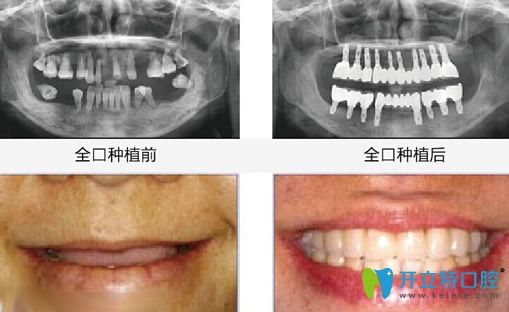

【全口牙缺失種植效果】

湛江致美口腔全口牙種植牙案例效果

種植牙前:全口牙齒缺失;

種植牙顧客評(píng)價(jià):由于牙齒掉光了,平時(shí)只能吃些稀飯和面條之類的食物,所以身體也不如以前好了,在女兒的帶領(lǐng)下到湛江致美做了全口牙種植牙,沒(méi)想到當(dāng)天回家就能吃東西,而且看著也和真牙沒(méi)什么兩樣!